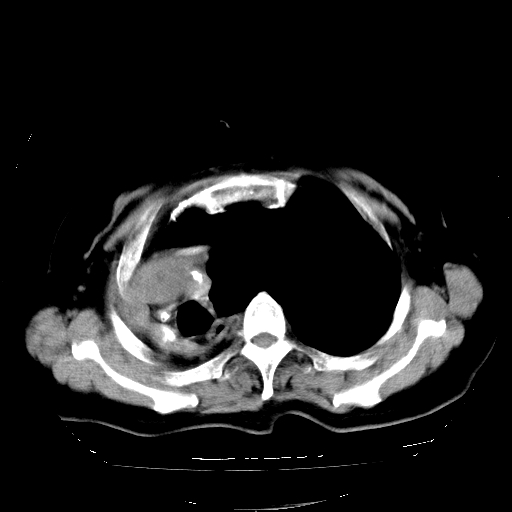

标题: CT23991:女,72岁,咳嗽、憋气一周。 [打印本页]

女,72岁,咳嗽、憋气一周,十年前曾患肺结核及胸膜结核。

右侧毁损肺,右侧纵隔疝

右侧毁损肺,右侧纵隔疝,左肺代偿!

1.右侧损毁肺伴胸膜钙化,2.左肺小结节灶,良性可能大,注意复查。3.肝脏左叶囊肿。4.先天性一侧肺不发育待出外(右侧胸廓无明显塌陷)。对比原片应该非常有帮助。

右侧肺毁损,左肺代偿性肺气肿,纵隔疝。